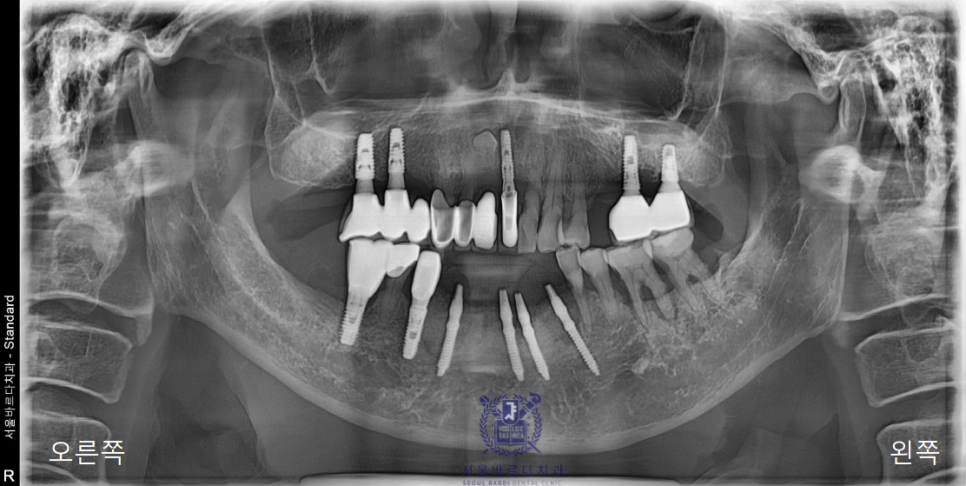

앞니 임플란트 잘하는곳 찾다가 소문 듣고 찾아오셨다고합니다.

앞니가 많이 붓더니 한참을 아프다가 흔들리기 시작했다고하셔서

일단 파노라마 사진을 찍어 전체적인 상태를 체크해드렸습니다.

이미 다수의 보철과 임플란트를 하셨고,

앞니쪽은 조금 더 자세하게 보기위해 치근단 엑스레이를 추가로 촬영하였습니다.

양쪽 송곳니 두개를 이용해 앞니 6개의 보철을 사용하고계셨는데

지지해주던 양쪽 송곳니쪽에 문제가 생겨서

염증이 이미 많이 진행된 상태였습니다.

왼쪽 위 역시 가장 이상적인 위치에 성공적으로 임플란트를 식립하였습니다.

아래 앞니는 6개의 치아를 안정적으로 유지할 수 있는

견고한 4개의 뿌리를 식립하였고

왼쪽 위는 큰어금니 다음으로 중요한 역할을 수행할 작은

어금니에 맞는 사이즈로 식립하였습니다.